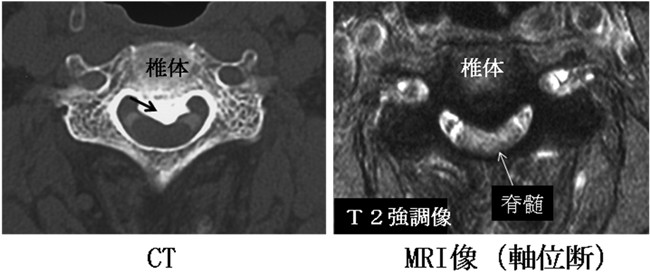

単純X線検査、CTで靭帯の骨化を認めれば頚椎OPLLと診断されます。また、MRIによって脊髄の圧迫の程度を評価することもできます。